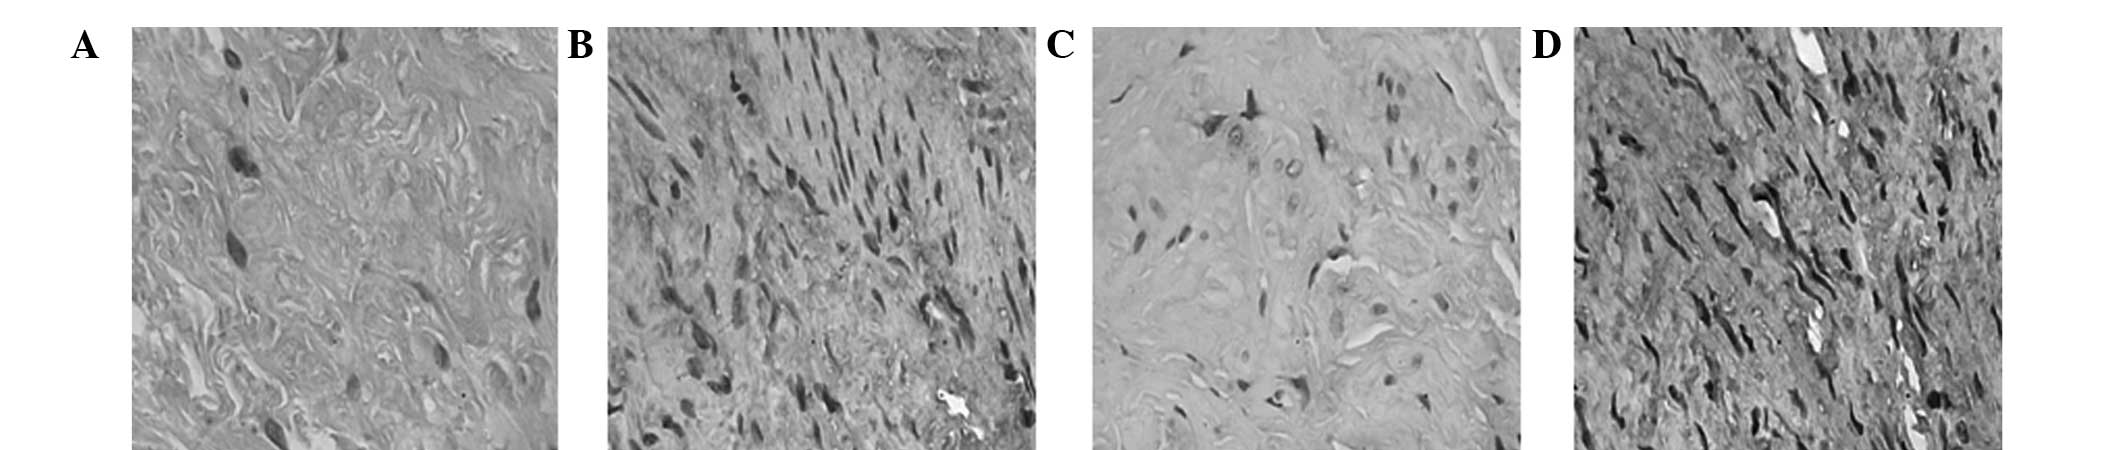

Expression of Type I collagen protein

In the control group, Type I collagen proteins in the cardiac ligaments, sacral ligaments and paraurethral tissues were asymmetrically stained. The proteins were arranged as ribbons with diffuse distribution or focal adhesion (Fig. 3A). In the POP or POP with SUI groups, Type I collagen proteins in the cardiac ligaments, sacral ligaments and paraurethral tissues were stained and distributed in unusual fractions (Fig. 3B).

Expression of Type I collagen in the (A) POP and POP with SUI and (B) control groups. Expression of Type III collagen in the (C) POP and POP with SUI and (D) control groups (magnification, ×200). POP, pelvic organ prolapse; SUI, stress urinary incontinence.

Expression of Type III collagen protein

In the control group, Type III collagen proteins in the cardiac ligaments, sacral ligaments and paraurethral tissues were stained with diffuse distribution or focal adhesion (Fig. 3C). In the POP and POP with SUI groups, Type III collagen proteins in the cardiac ligaments, sacral ligaments and paraurethral tissues were marginally stained (Fig. 3D).